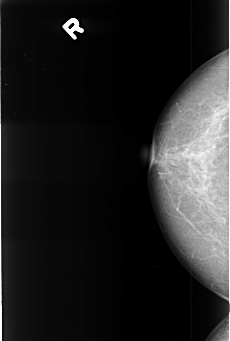

B_3397_1.RIGHT_CC

RIGHT_CC LINES 4424 PIXELS_PER_LINE 2984 BITS_PER_PIXEL 12 RESOLUTION 50 NON_OVERLAY